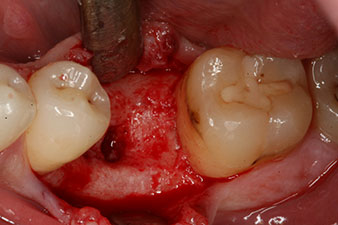

Fig. 2: Six weeks later there was an incompletely ossified alveolus in the region of the mesial root.

However, six weeks after the extraction incomplete ossification was found after preparation of the mucoperiosteal flap in the region of the former mesial alveolus.